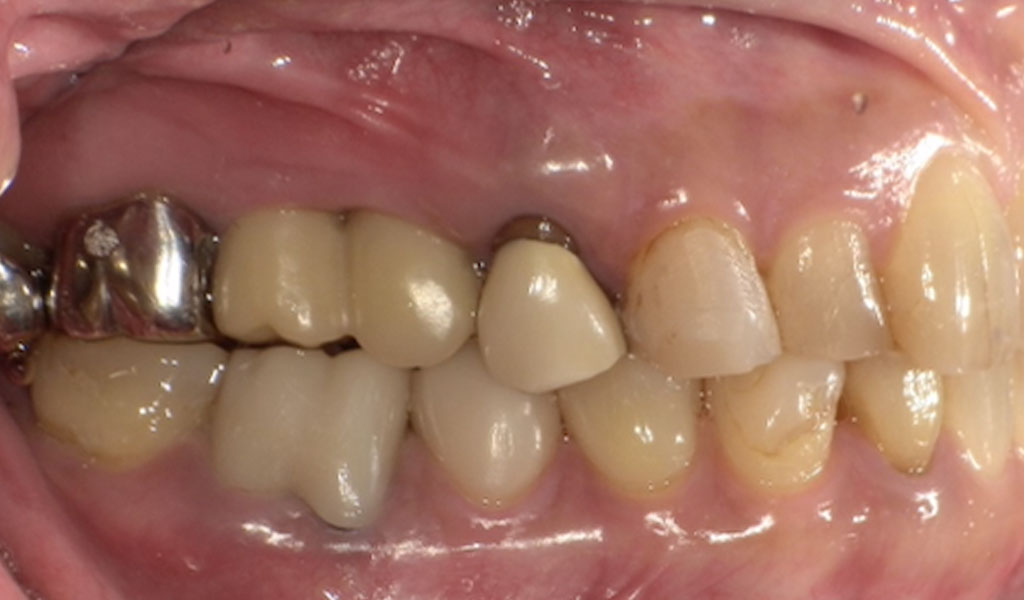

Before(右上5,6番)